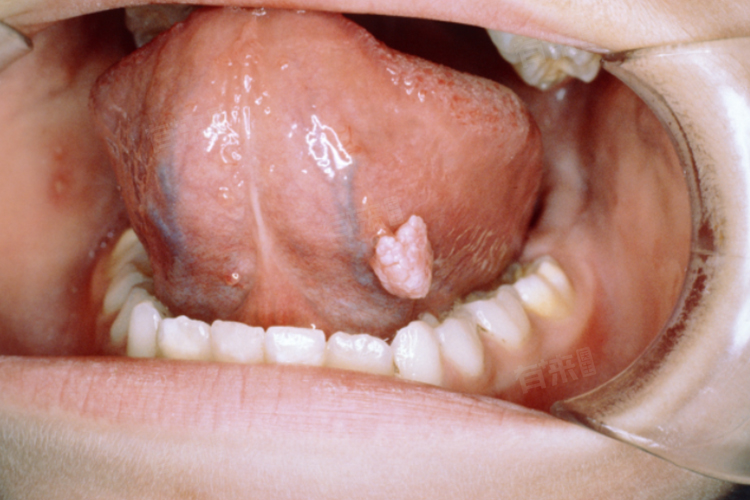

- 在口腔HPV感染的过程中,病毒主要侵犯口腔黏膜的上皮细胞。在潜伏期内,病毒可能处于静默状态,不引起明显的细胞病变或免疫反应。然而,随着病毒的复制和扩散,它可能逐渐引发口腔黏膜的炎症反应,导致红肿、疼痛、凸起物、溃烂等症状的出现。这些症状不仅影响患者的口腔健康和生活质量,还可能成为HPV传播给他人的途径。

2、注意观察口腔变化:定期对着镜子观察口腔情况,如果发现小疙瘩、异常增生或颜色变化等症状,应及时就医进行专业检查。